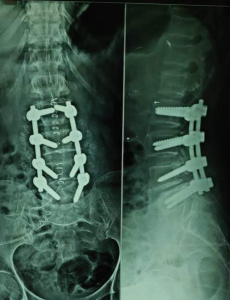

PROFILE TRAINING AND PRESENTATION Dr. Niranjanan Recieving Diploma SICOT degree in Rome, Italy Dr. Niranjanan being awarded fellowship certificate at Indian spinal injuries centre CLIINIC SOME OF Dr. NIRANJANAN's CASES